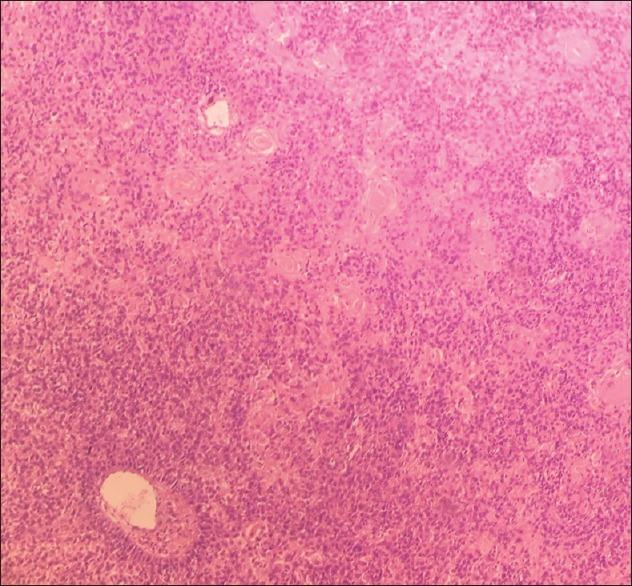

Carcinoma of the cervix is the second to fourth most common malignancy in women. It metastasizes most often to the lungs, bones, and liver. Skin involvement originating from cervical cancer is rare, even in the terminal stages of the disease. Cutaneous metastasis of cervical cancer usually presents as cutaneous nodules, papules/plaques, maculopapular rash, and diffuse inflammatory rash. We report a rare case (only the second reported case to the best of our knowledge) of a 50-year-old woman with cutaneous metastasis in form of fungating ulcerative growth on mons pubis as presenting feature of carcinoma cervix.

宫颈癌是女性中第二至第四常见的恶性肿瘤。它最常转移至肺、骨和肝脏。即使在疾病晚期,宫颈癌累及皮肤也很罕见。宫颈癌的皮肤转移通常表现为皮肤结节、丘疹/斑块、斑丘疹和弥漫性炎性皮疹。我们报告了一例罕见病例(据我们所知仅为第二例报告病例),一名50岁女性,以耻骨上蕈样溃疡性生长形式的皮肤转移作为宫颈癌的首发表现。